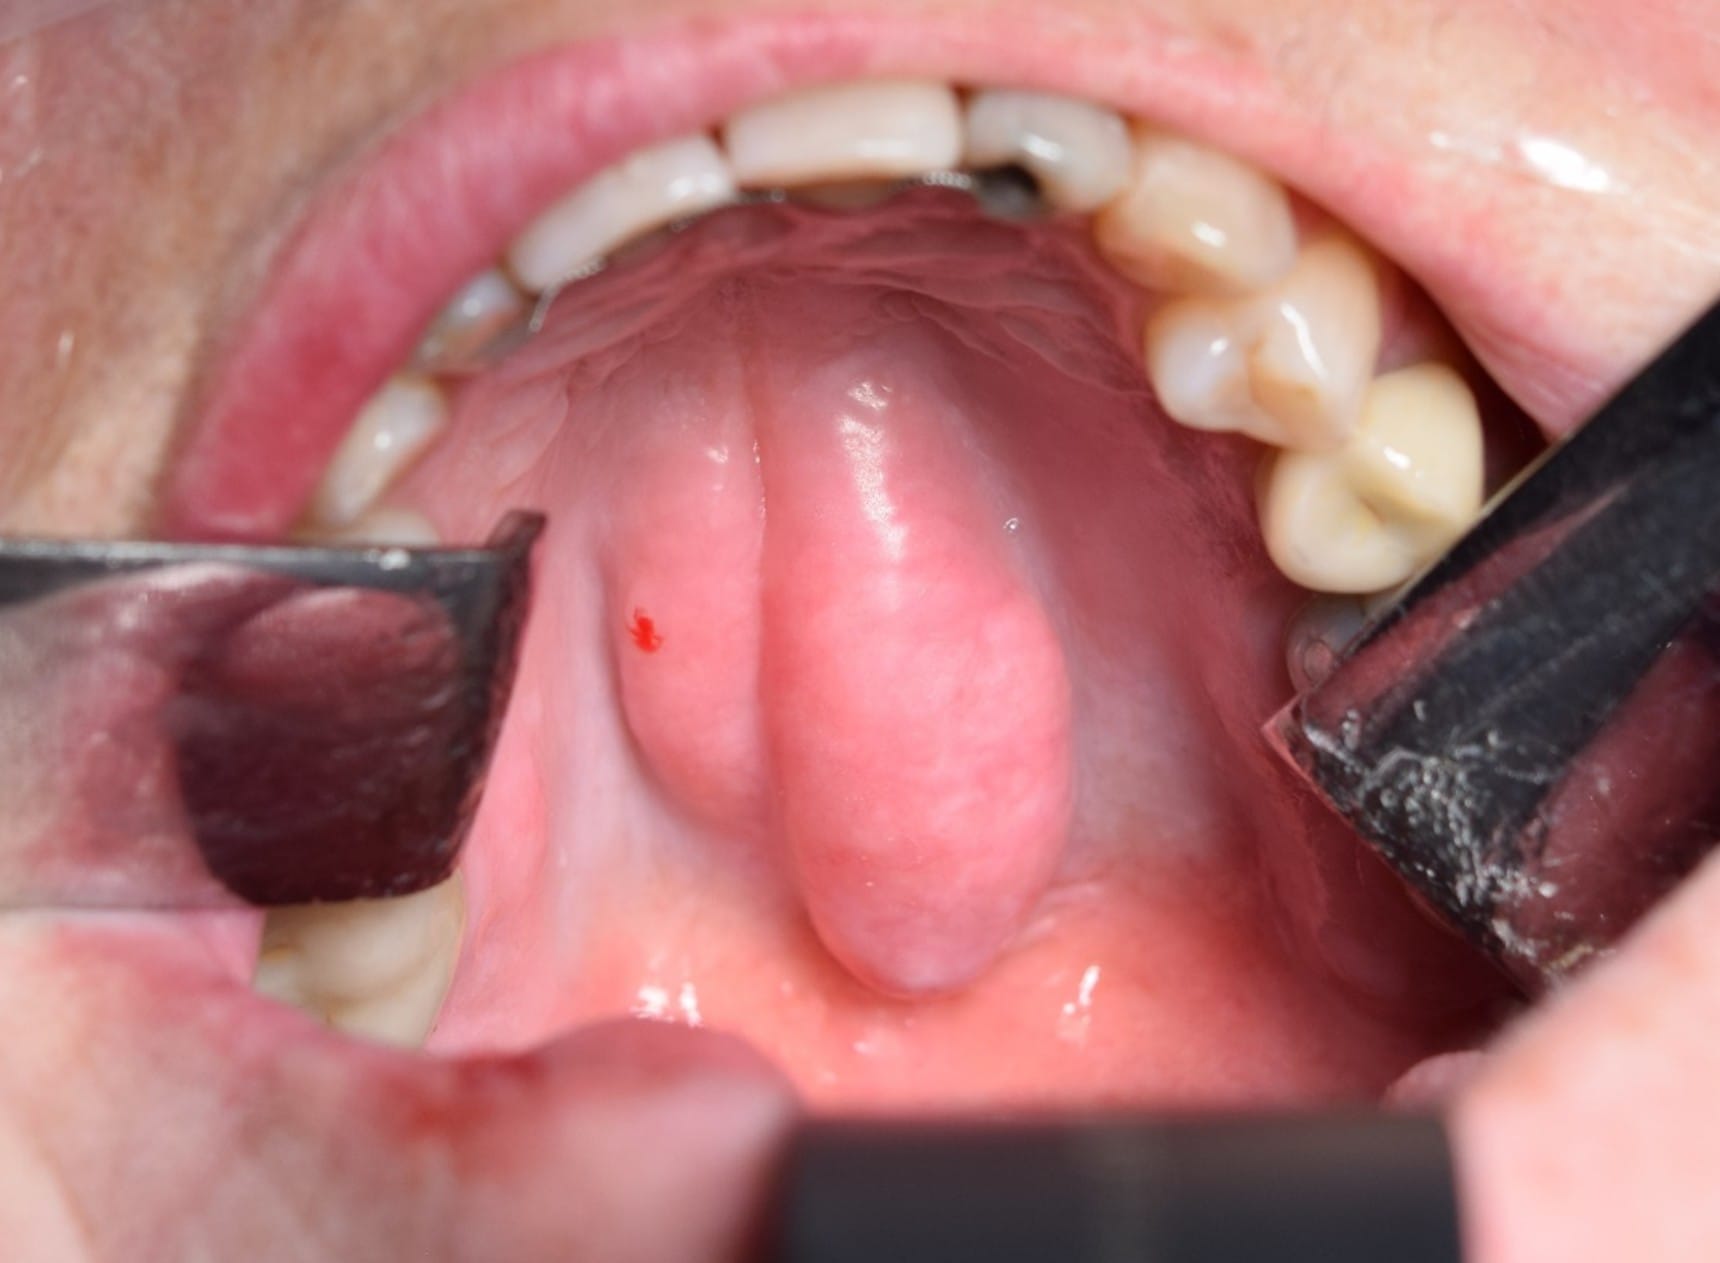

- Torus mandibularis (bild 1)

Torus Mandibularis

Torus mandibularis är en lobulerad hård förändring på lingualsidan av mandibeln bilateralt. Vid större torus kan det vara svårt för patienter att ta röntgen, de kan påverka uttalet, störa sväljfunktionen och orsaka smärta i slemhinnan under felaktigt utformade proteser.